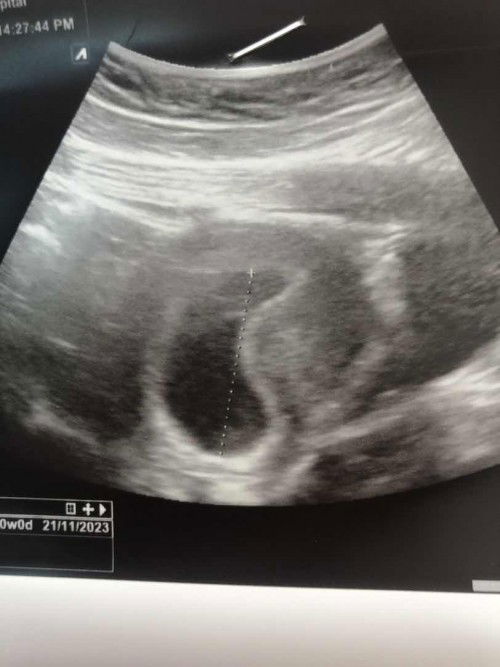

28 วีค น้ำหนักขึ้นเท่าไรกันบ้างคะแม่ๆ

บ้านนี้ 28 วีค ขึ้นมาแล้ว 8 โล กังวลว่าจะมากเกินไป เพราะก่อนท้องแม่หนัก 63 แล้วค่ะ ตอนนี้ 71 แล้ว 😂 #ท้องแรกคะ อยากปรึกษาแม่ๆ กินยังไงให้ลงลูกบ้างคะ ไม่อยากให้ค้างที่แม่เยอะเลยค่ะ กลัวลดไม่ลง #ขอคำแนะนำหน่อยค่ะ